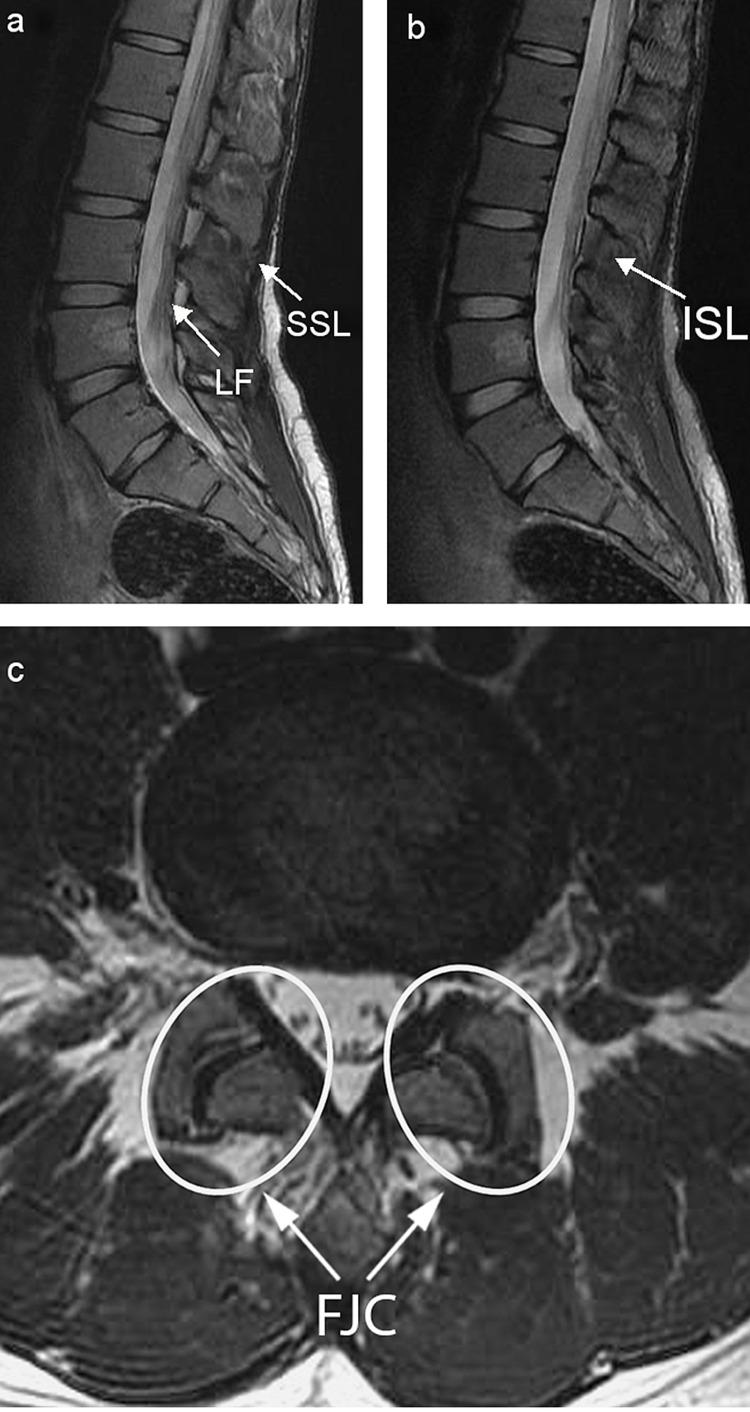

The soft tissues surrounding the spine play a primordial role in its stability, the most important of which are located posteriorly and are deemed the posterior ligamentous complex (PLC). Injuries to the PLC in the setting of thoracolumbar trauma are often dreaded and little attention has been given to them in the management protocols of thoracolumbar trauma. This review aims to summarize and contextualize current concepts in PLC injuries of the thoracolumbar spine with the aim to provide a clear guide for clinical management. Injuries to the PLC may be suspected on the clinical exam but are often missed, leading to serious complications, including instability and neurological compromise. The diagnosis is often made indirectly by spinal radiographs and CT-scanning or by direct visualization of soft tissues via magnetic resonance imaging. The latter remains the standard imaging modality and is mandatory for patients with a high suspicion of PLC injury. PLC injuries are associated with vertebral fractures and follow a progressive pattern of severity, depending on the mechanism of injury and extent of trauma. Surgical management is warranted, as PLC damage renders the spine unstable. Although fusion was once the standard of care and remains applicable for certain patients, recent endeavors of temporary spinal fixation without fusion are increasingly gaining traction in patients with PLC injuries. In conclusion, PLC injuries are challenging as they are often missed, poorly understood, and are not easily managed. Proper diagnosis and management are crucial to avoid long-standing complications such as spinal instability. Considering the paucity of available data on such an important topic in thoracolumbar trauma, this review article aims to contextualize current concepts in PLC injuries in order to demystify this sparsely covered subject.

脊柱周围的软组织对其稳定性起着至关重要的作用,其中最重要的位于脊柱后方,被称为后韧带复合体(PLC)。在胸腰椎创伤情况下,PLC损伤往往令人担忧,而在胸腰椎创伤的管理方案中,对其关注较少。本综述旨在总结和梳理胸腰椎PLC损伤的当前概念,以便为临床管理提供清晰的指导。PLC损伤在临床检查中可能被怀疑,但常常被漏诊,从而导致严重并发症,包括脊柱不稳定和神经功能损害。诊断通常通过脊柱X线片和CT扫描间接做出,或通过磁共振成像直接观察软组织。后者仍然是标准的成像方式,对于高度怀疑PLC损伤的患者是必需的。PLC损伤与椎体骨折相关,并根据损伤机制和创伤程度呈现出逐渐加重的严重程度模式。由于PLC损伤会使脊柱不稳定,因此需要进行手术治疗。虽然融合术曾经是标准的治疗方法,并且仍然适用于某些患者,但最近在PLC损伤患者中,不进行融合的临时脊柱固定方法越来越受到关注。总之,PLC损伤具有挑战性,因为它们常常被漏诊、理解不足且不易处理。正确的诊断和管理对于避免诸如脊柱不稳定等长期并发症至关重要。鉴于在胸腰椎创伤这一重要主题上可用数据匮乏,本文旨在梳理PLC损伤的当前概念,以揭开这个研究较少的主题的神秘面纱。